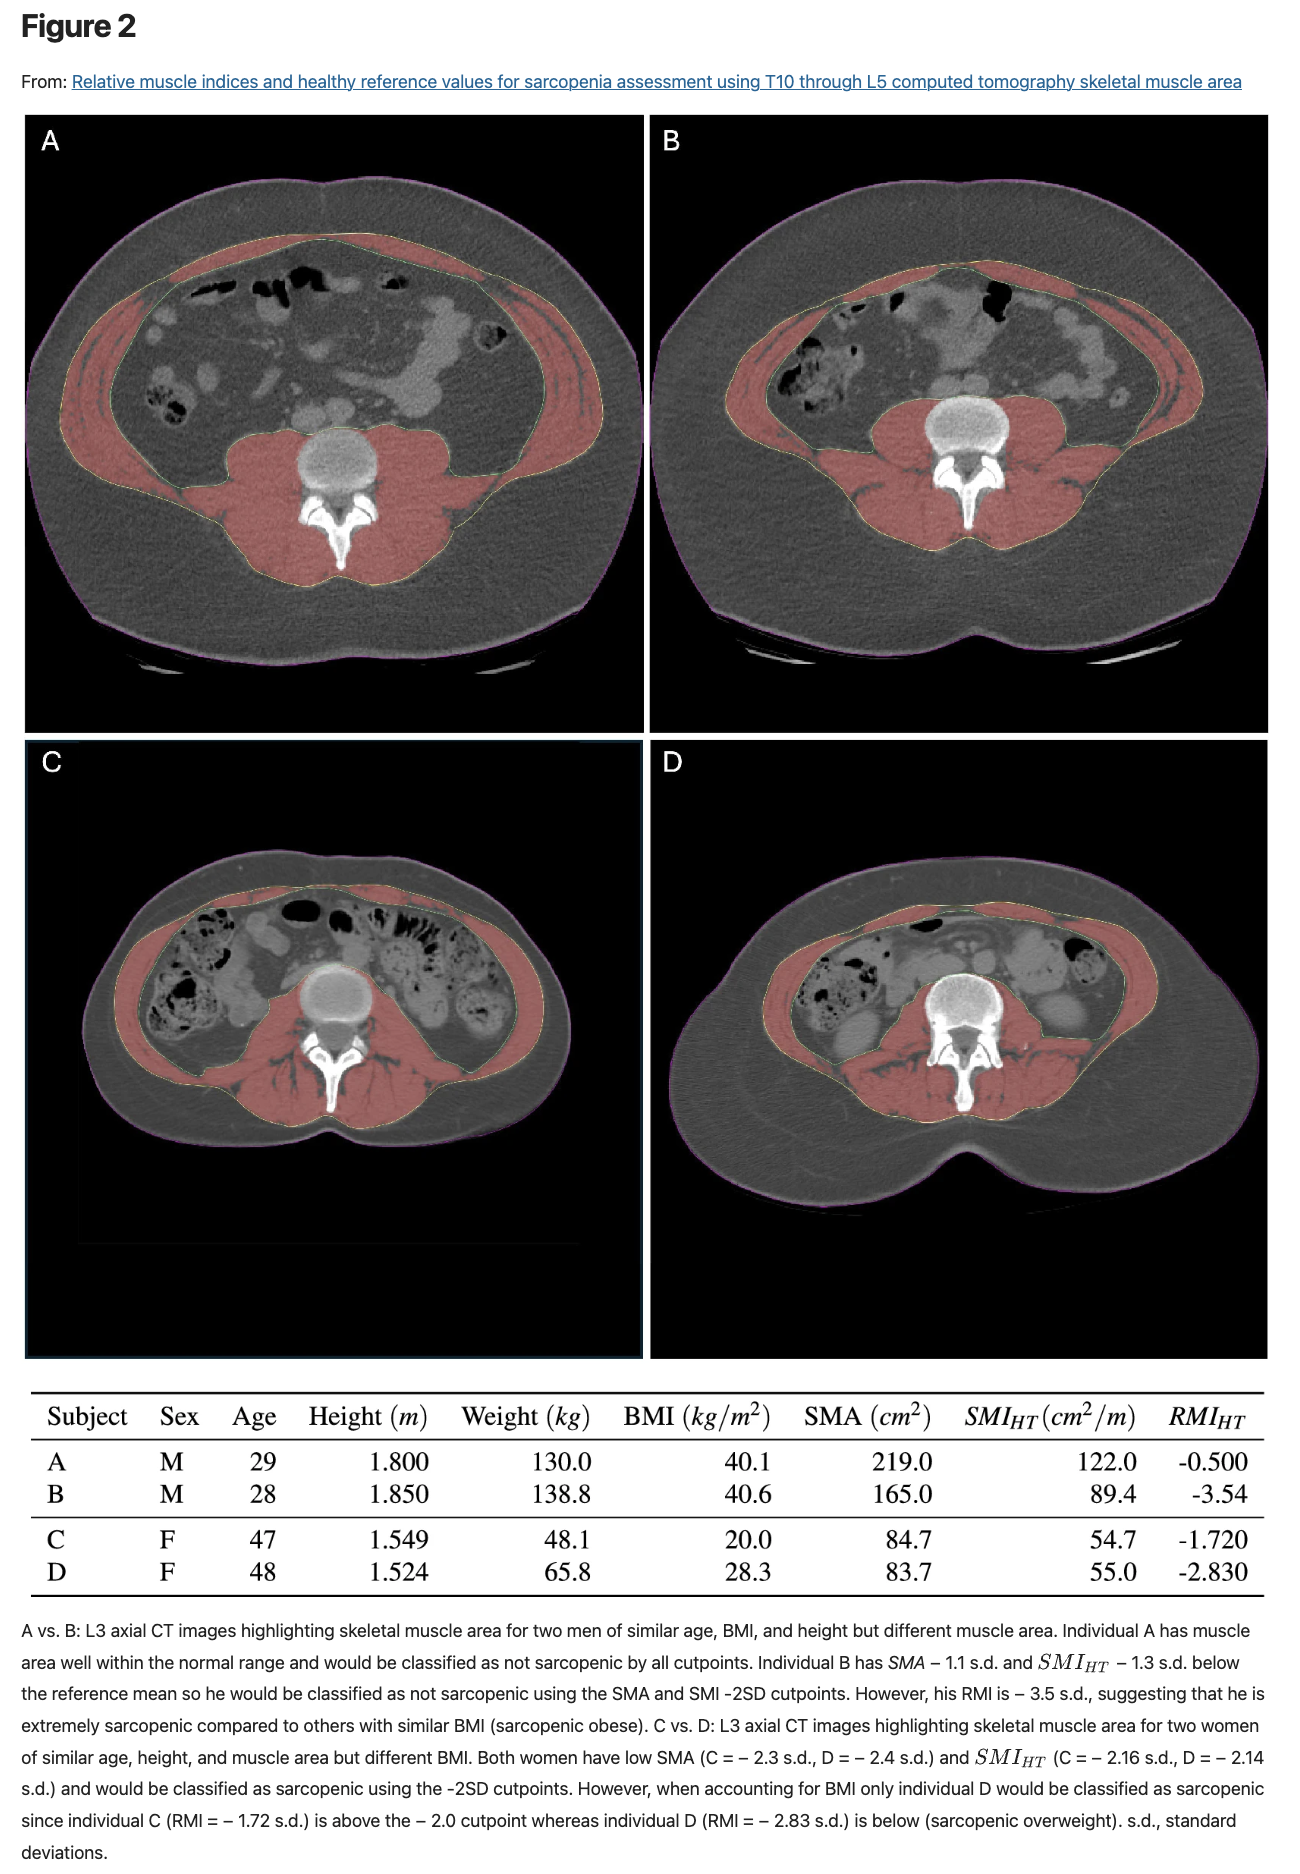

Most people are familiar with body mass index (BMI), a simple equation that normalizes body weight based on its underlying relationship to height.  Similarly, we developed the concept of the relative muscle index (RMI), which normalizes torso musculature based on body size (height and BMI).  Values above zero indicate ‘more muscular’ BMI, and values below zero indicate ‘less muscular’ BMI.

We believe our equations are correct and helpful, but they can be intimidating, so we provided images in our publication showing real examples of how they might change individual assessments of sarcopenia for people that might appear to be quite similar based on other standard metrics.

Figure from one of Brian Derstine's articles showing CT images of four human torsos.

CT scans showing real examples of how individual assessments of sarcopenia for people that might appear to be quite similar based on other standard metrics (like height, weight and BMI) would change when measuring RMI.